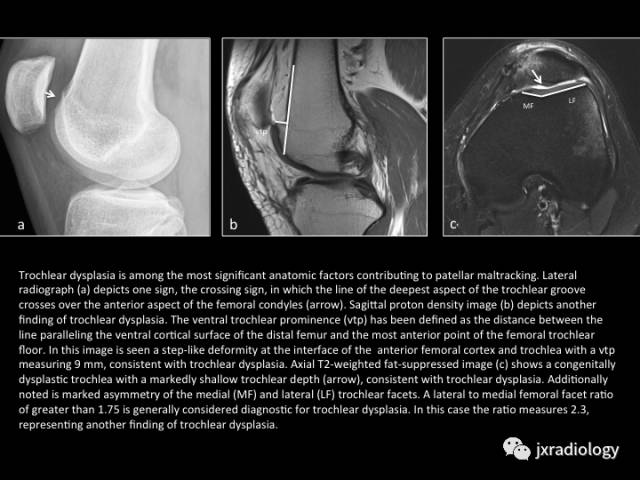

Fig. 9: Trochlear dysplasia

图9:(股骨)滑车发育不良

股骨滑车发育不良是指滑车沟前部的几何外形和深度存在的解剖学异常。可引起髌骨轨迹不良或慢性膝关节不稳。